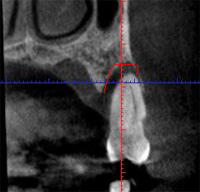

CT診断すると以下の赤線まで骨がなくなっています。

![]() |

抜歯をしてインプラントをおこなうとき患者さんの負担を考え、第一選択は抜歯即時無切開インプラントと考えてますが、このように骨がない場合は、抜歯と同時に骨を造る処置をおこなってから数ヶ月たってインプラント治療をおこないます。